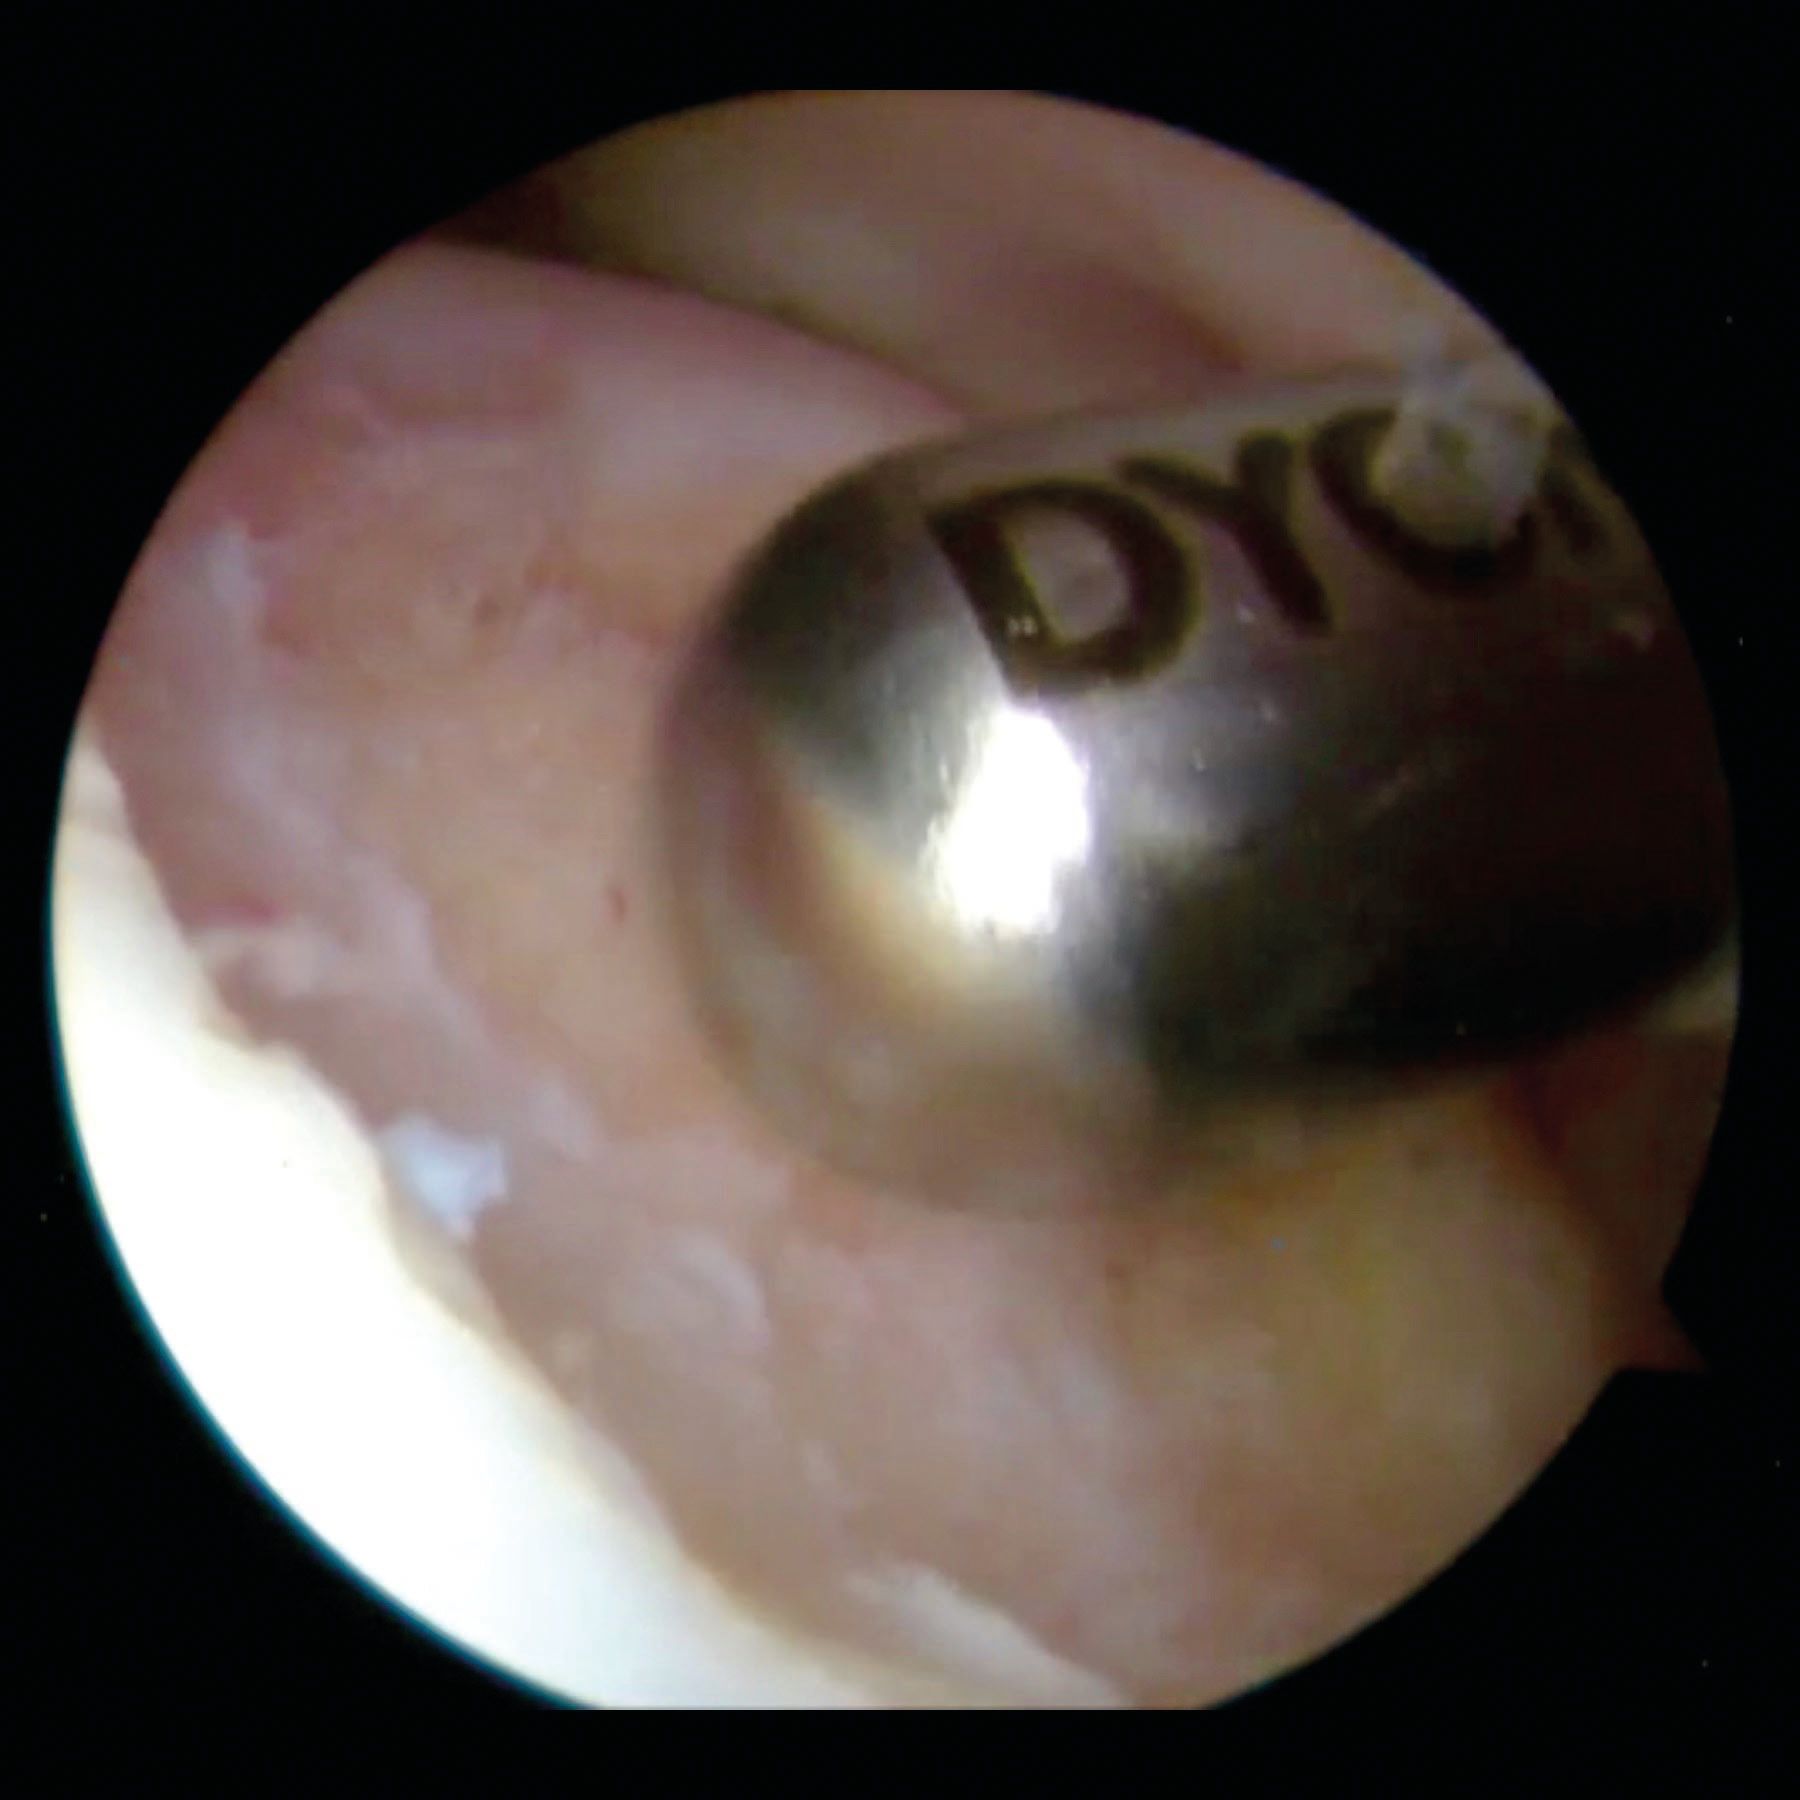

The posterior lateral humeral defect was first described by Malgaigne in 1855, then by Broca and Hartmann in 1890. It was then classified by Hill and Sachs in 1940 [10] and this is the usual name nowadays. The Hill-Sachs defect is a posterior lateral compression fracture on the humeral head which happens during an anterior dislocation when the glenoid anterior rim hits the posterior part of humeral head. Figure 1.

It is located at the posterior aspect of the humeral head. Usually, a small HSL is located close to the greater tuberosity attachment of the infra-spinatus, whereas a large HSL extends more medially.

The concept is to fill (remplissage means filling in french) the humeral defect with soft tissue (posterosuperior capsule along with the infraspinatus tendon). The healing process of the capsule in the defect will convert the intra-articular Hill-Sachs lesion in an extra-articular lesion incapable of engaging with the glenoid. This procedure is combined with the treatment of the anterior capsulo-labral lesion (Bankart). The two procedures are concomitant and performed arthroscopically. Figure 3.